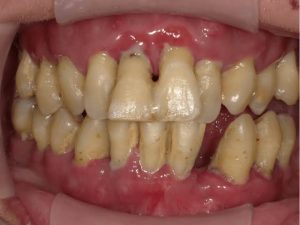

歯周病とは、細菌の感染によって引き起こされる炎症性疾患で、歯の周りの歯ぐき(歯肉)や、歯を支える骨などが菌によって溶かされてしまう病気です。

歯と歯肉の境目(歯肉溝)の清掃が行き届かないと、そこに多くの細菌が停滞し歯肉の辺縁が炎症を起こして赤くなったり、腫れたりします。痛みはほとんどの場合ありません。

さらに進行すると膿がでたり歯が動揺してきて、最後には歯を抜くことになってしまいます。